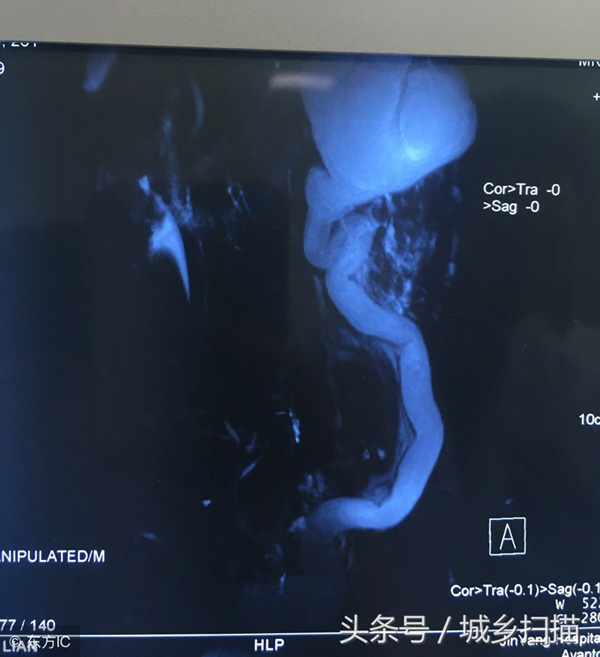

Vương Khai Luyện một lần bị đau dữ dội ở phần lưng eo, vì không chịu nổi mới đến bệnh viện kiểm tra. Sau khi kiểm tra, chụp X quang các bác sĩ phát hiện anh Vương có 4 quả thận. Bác sĩ cho biết, thận trên bên trái của anh bị ứ nước nghiêm trọng, bao phủ và chèn ép thận dưới bên trái, kèm theo nhiễm trùng gây ra một loạt các triệu chứng như đau lưng eo và sốt.

Vương Khai Luyện có 4 quả thận, mỗi bên 2 quả, mỗi bên có hệ thống cung cấp máu và hệ thống bài tiểu. Hai quả thận ở mỗi bên dài như một em bé dính liền. Thận của một người bình thường có kích thước tương đương với nắm tay của người đó. Bốn quả thận của Vương Khai Luyện nhỏ hơn người bình thường và chỉ bằng cỡ nắm tay của em bé.

Bác sĩ nói rằng, thận của Vương Khai Luyện xuất hiện ổ bệnh là thận trên bên trái, bên trong có chứa lượng lớn chất lỏng. Theo kết quả kiểm tra hình ảnh, tràn dịch đã khiến thận trở nên to gấp 3 đến 5 lần so với ban đầu. Nếu thận trên bên trái không được loại bỏ kịp thời, đồng thời nhiễm trùng sẽ càng nghiêm trọng hơn và cũng có thể gây nguy hiểm cho các thận khác.